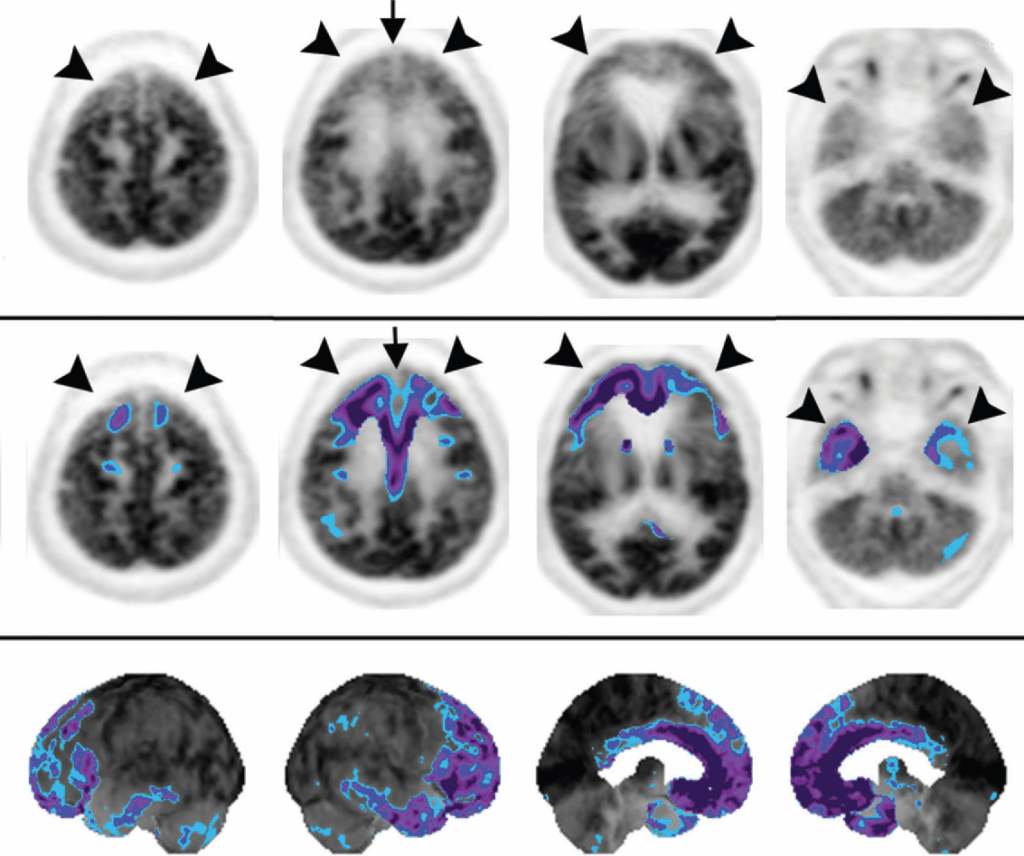

Demenza Fronto-Temporale (FTD)

La Demenza Fronto-Temporale si manifesta con un ipometabolismo localizzato nei lobi frontali e temporali anteriori, con un coinvolgimento caratteristico anche del giro del cingolo anteriore. Questo aspetto rappresenta un importante fattore di differenziazione rispetto all’AD, in cui il cingolo anteriore è invece risparmiato. Esistono varianti della FTD, come la variante a predominanza frontale (associata a cambiamenti comportamentali) e la variante temporale (o demenza semantica), caratterizzata da disturbi del linguaggio.

- Degenerazione Corticobasale: questa patologia è caratterizzata da una marcata asimmetria dell’ipometabolismo, che coinvolge la corteccia sensomotoria e, omolateralmente, i gangli della base o il talamo.

- Atrofia Cerebrale Posteriore (PCA): considerata una variante atipica dell’AD, la PCA si presenta con un pattern di ipometabolismo parietotemporale e occipitale posteriore, ma con il coinvolgimento aggiuntivo delle cortecce associative visive laterali, che spiega i deficit visivi complessi tipici di questa sindrome.